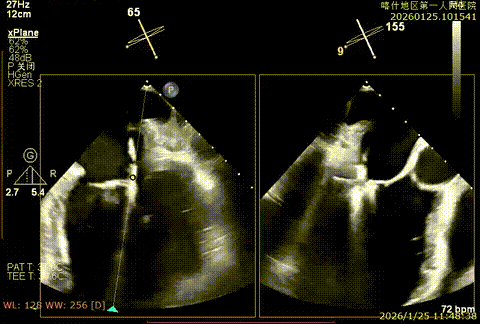

该例患者为VFMR,术前制定手术策略:患者二尖瓣重度反流,后叶严重栓系,心房心室扩大。患者瓣口面积4.5cm2,预计使用两枚XTR解决患者瓣叶脱垂和反流。考虑到先于2区进行钳夹,应该能获得足够的房间隔穿刺高度。术中经不断调整穿刺位点,最终穿刺高度4.4cm。成功穿刺后将第一枚XTR送入二尖瓣正上方,进行弹道测试Orientation调整后,最终定位于2区正上方下左心室。第一枚夹子在左室成功捕捞和钳夹瓣叶后,瓣叶反流程度显著降低,夹子外侧仍见部分反流,随后在第一枚夹子外侧再次放置一枚XTR,瓣叶反流程度进一步降低至微量。通过TEE观察,二尖瓣双孔组织桥稳定,跨瓣压差3mmHg,肺静脉逆流改善明显,手术安全结束。

X-plan重度反流

3D enface后叶栓系

3D enface观察反流

第一枚二尖瓣夹定位

第一枚XTR捕捞夹持

第二枚XTR弹道测试

第二枚成功钳夹

反流充分降低

术后压差3mmHg